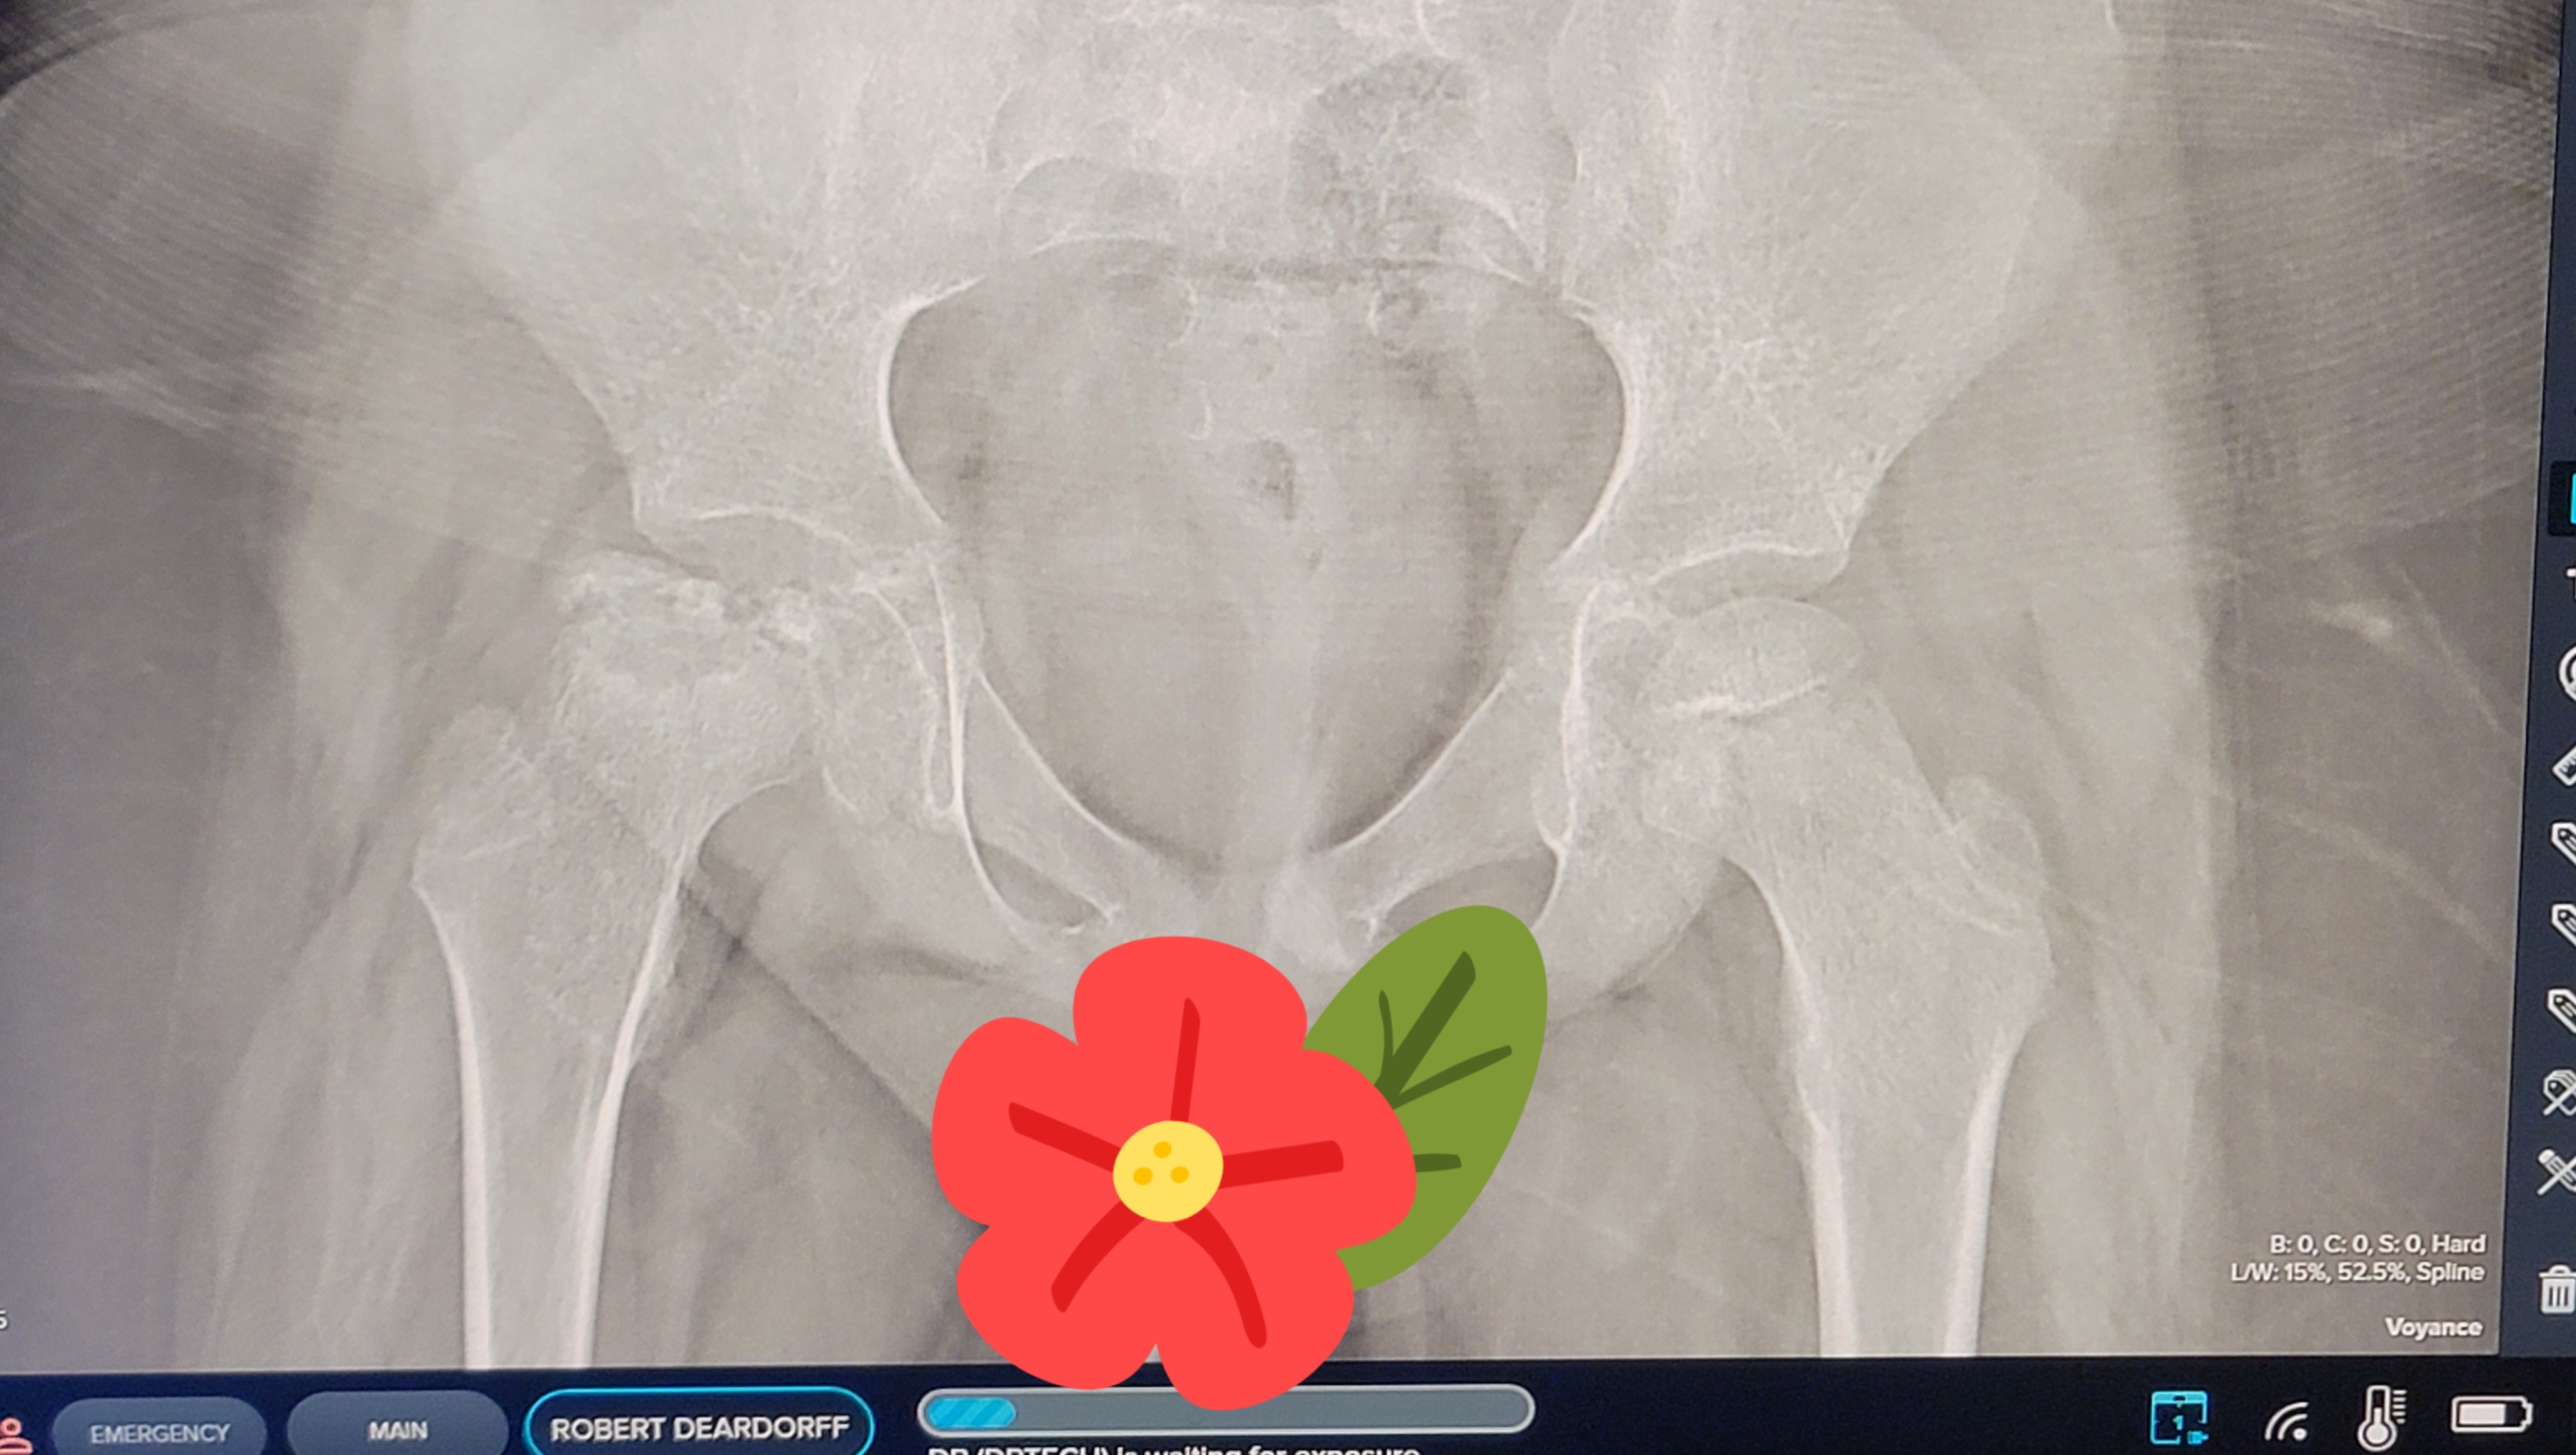

His next surgery is scheduled for May 7th, 2026 at Shriners Children’s Hospital in Honolulu with Dr. Pellet and Dr. Izuka. This procedure will remove the metal hardware that was placed in his femur during the osteotomy.

X-ray taken November 2025, showing bone re-growth